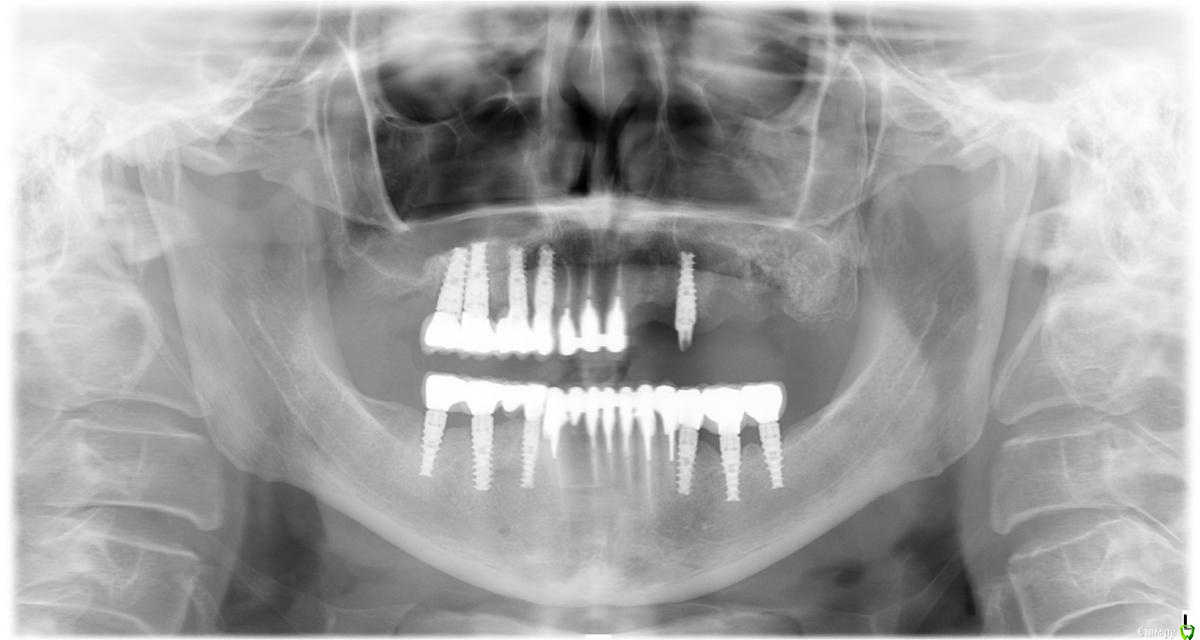

jell273 Опубликовано 12 июля, 2016 Поделиться Опубликовано 12 июля, 2016 Всем доброй ночи. В прошлой теме http://forum.stom.ru/topic/10643-ochen-slozhnoe-protezirovanie-pomogite/, я писала о плане протезирования и установки имплантов. Все манипуляции с зубами , были закончены в 2011 году и радостно ходила до ноября 2015 года. Пока верхние, левые импланты не стали качаться и не выпали,, Потом оказалось, что у меня Гаймороэтмоидит. Болей особо не было и доктор , мне через разрез в десне, пытался, почистить гайморову пазуху. Толку было ноль,. Потом был 1 мед. Проколы, уколы, таблетки и.т д. Вроде все вылечили. Хотя до имплантации , гайморитов не было. Сейчас сделали сьемный протез, . К осени, доктор хочет нарастить кость , с синуслифтингом. Подождать месяцев 6???.. Потом поставит импланты, и только потом через еще несколько месяцев коронки. Гарантии, что, что то пойдет не так никто не дает. Не лор, не имплантолог. Врач у меня, очень хороший и грамотный. У меня, к вам вопрос, уважаемые врачи. Были ли случаи, выпадения имплантов, через 4 года??? Или , мне одной, так не повезло??? Шок уже прошел. Теперь с врачем , пытаемся действовать очень осторожно. Остальные импланты стоят на месте и слава богу не шатаются. Снимки прилагаю. Спасибо Ссылка на комментарий

Bier Опубликовано 14 июля, 2016 Поделиться Опубликовано 14 июля, 2016 Судя по всему кость в пазухе не образовалась. На мой взгляд нужно сделать нормальную ревизию, если старый материал не окостенел, его нужно вычистить. Ссылка на комментарий

jell273 Опубликовано 14 июля, 2016 Автор Поделиться Опубликовано 14 июля, 2016 При имплантации в 2011 году синуслифтинг проводился?Да, проводился. Стоматолог, после выпадения имплантов и найденном гаймороэтмоидит, мне через разрез в десне, сделал гайморотомию. Ощущение было не забываемое. Может он тогда и ревизию сделал??? Хочется, после подсадки кости, что бы нормально прижились импланты и не выпали через несколько лет. Меня синуслифтинг и имплантация не пугают, это все нормально обычно проходит, но если, что то пойдет не так , после имплантации, еще одну гайморотомию , мне бы не хотелось. Тем более, что она будет проходить уже у лора в 1 меде , и под наркозом. Думаю, что проколами будет не обойтись. Можно конечно со сьемным протезом ходить, но не хотелось бы. Ссылка на комментарий